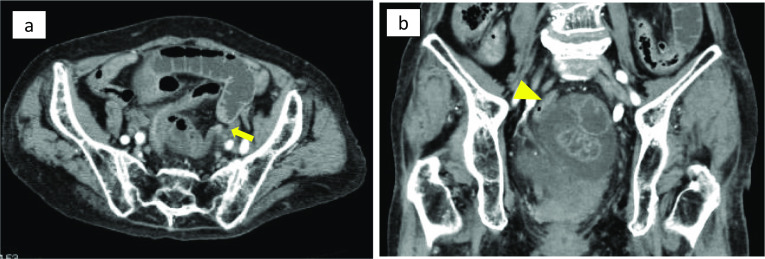

An 87-year-old woman presented with the chief complaint of lower abdominal pain and nausea. She was referred to our hospital with persistent lower abdominal pain and vomiting. On physical examination, mild tenderness was present in the lower abdomen. Blood test revealed elevated white blood cell count (12,200 /μl) and C-reactive protein levels (2.2 g/dl), with no other pertinent findings. The patient had diabetes and high blood pressure and had previously undergone total hysterectomy for uterine fibroids. Contrast-enhanced computed tomography showed beak-like changes in the small intestine, closed loop formation with reduced contrast effect, and localized ascites on the left side of the rectum in the pelvis (Fig. 1a, b). Strangulation small bowel obstruction was diagnosed, and emergency laparotomy was performed. The small intestine was found to invade the peritoneal reflection on the left side of the rectum (Fig. 2a, b). The final diagnosis was pararectal fossa hernia. The incarcerated small intestine was released, and no bowel resection of the same site was required because the intestinal blood flow disorder was reversible. The 4-cm hernia phylum was observed and closed by simple suture (Fig. 2b). The patient had a good postoperative course and no recurrence.

Fig. 1.

Computed tomography before treatment. a Abdominal computed tomography shows extensive small intestinal dilation and beak-like changes in the small intestine (arrow) on the left side of the pelvis. b A closed loop with reduced contrast effect is formed on the left side of the rectum (arrow head), and localized ascites is observed